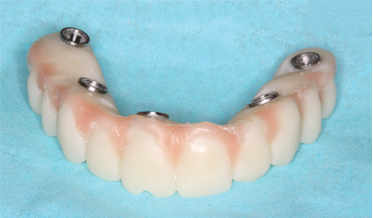

Adapting the Digital Reference Denture Technique for Full-Arch Cases Using a Novel Fixed Attachment System